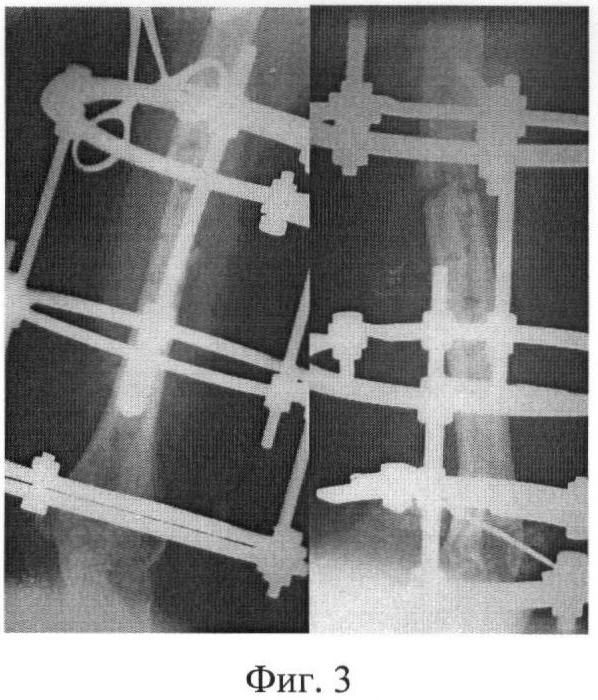

25.04.07 г. в СарНИИТО произведена операция: удаление пластины, замещение кортикального дефекта аутотрансплантатом (фиг.2), комбинированный чрескостный остеосинтез плеча (фиг.3) по предлагаемой методике. Рана зажила первичным натяжением. В послеоперационном периоде наблюдалось воспаление мягких тканей вокруг проксимального стержня, который был удален. После недельного консервативного лечения 16.08.07 г. ввели дополнительный стержень на этом же уровне. 23.10.07 г. демонтаж АВФ. После клинико-рентгенологического сращения (фиг.4) аппарат внешней фиксации 23.10.07 г. был демонтирован. Общий срок фиксации составил 6 месяцев.